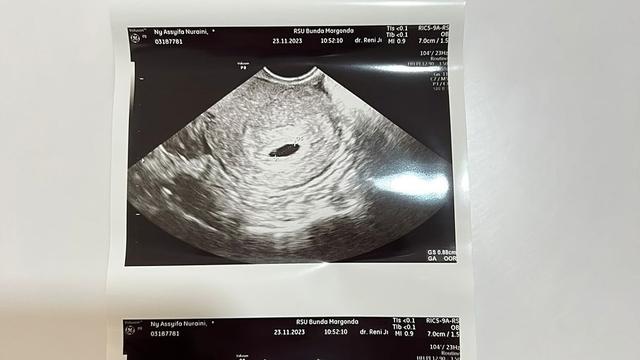

1. Pada Kamis, 23 November 2023, Syifa adik Ayu Ting Ting menjalani USG kehamilan keduanya.

2. Rupanya, usia kandungan Syifa saat USG kehamilan sudah memasuki 5 minggu.